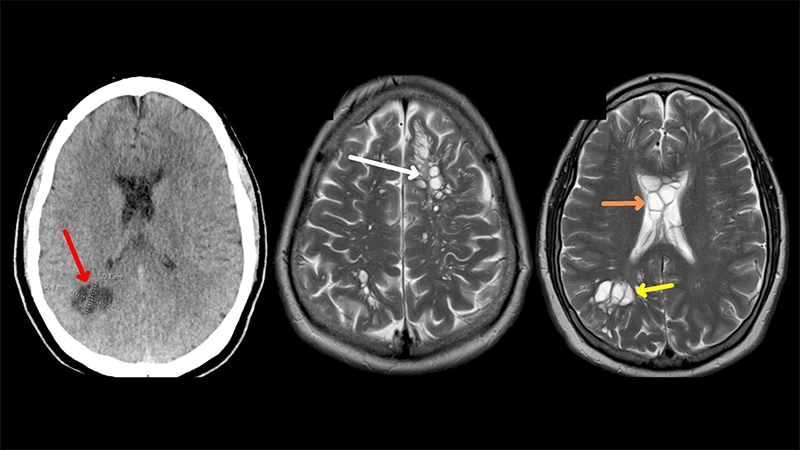

A middle-aged man from Florida with a history of migraines went to the doctor as his headaches were becoming worse and weren’t responding to his usual drugs. The 52-year-old was sent for a CT scan, which revealed something alarming: his brain was infested with tapeworm cysts.

In this case, the parasite has reverted to the cysticercus form and while seeking out muscle has accidentally made its way into the brain via the blood stream resulting in a condition called neurocysticercosis. The parasite has still made the best of the situation, as it could carry on its lifecycle if scavenged following the death of the host.

Neurocysticercosis is also treated with antihelminthics, but the resulting immune response in the brain can cause more harm than good and needs to be turned down with anti-inflammatory drugs.

The reported patient opted for this dual treatment and is recovering with reduced brain lesions and headaches.